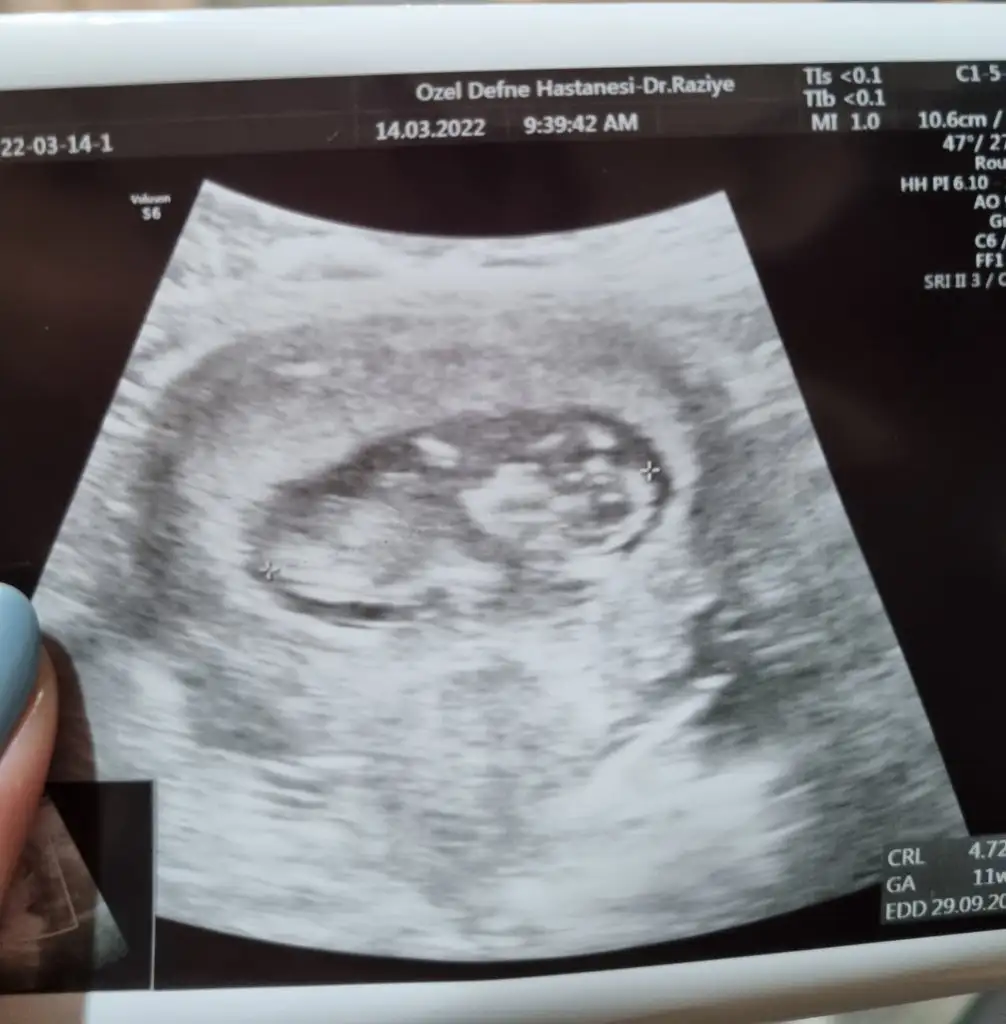

11+2 de olan görüntümüz karından bakıldı bana da bi tahminde bulunur musunuzSelam Kızlarbir çok kişi gruplardan beni bilir. Yine yetiştim imdatlara

canım senin prensesi geliyor11+2 de olan görüntümüz karından bakıldı bana da bi tahminde bulunur musunuz